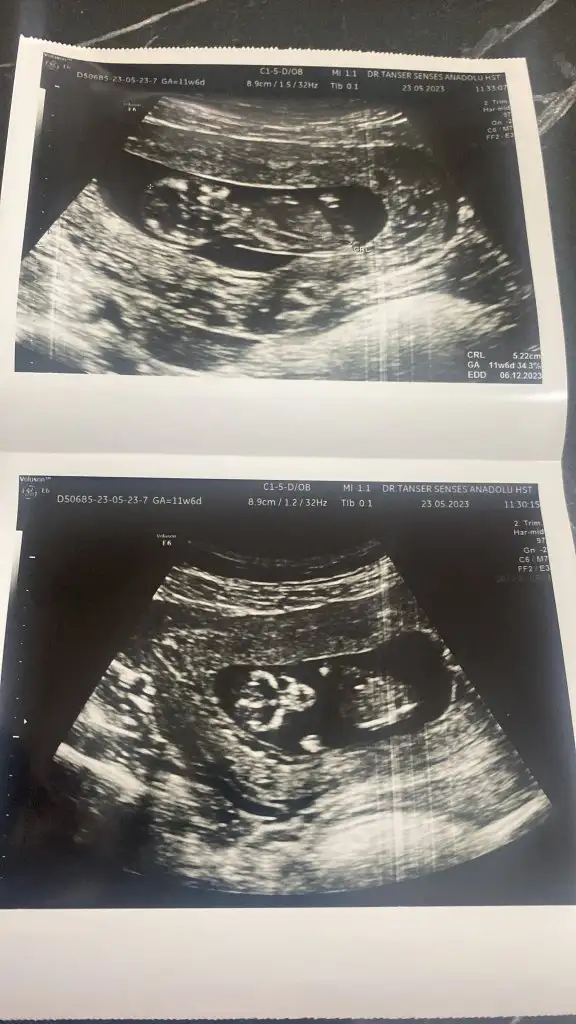

Nub teorisine göre kız görünüyor

TeşekkürlerNub teorisine göre kız görünüyorsağlıkla doğsun

Nub teorisine göre kız görünüyorsağlıkla doğsun

Nub’a göre yorum yapmak için bacak arasında nub kısmının görünmesi gerek. Yukarıdaki görüntüde diğer kızların pipi dediği şey nub. Bu teoriye göre nub yere paralelse kız, havaya doğru açı yapıyorsa erkekmiş. Sizde o kısmı göremediğimden yorum yapamadım

Teşekkür ederim sağlık olsunNub’a göre yorum yapmak için bacak arasında nub kısmının görünmesi gerek. Yukarıdaki görüntüde diğer kızların pipi dediği şey nub. Bu teoriye göre nub yere paralelse kız, havaya doğru açı yapıyorsa erkekmiş. Sizde o kısmı göremediğimden yorum yapamadım

Amin hepsi sağlıklı olsun bebişlerimizin, cinsiyeti de merak ediyor tabi insan. Ben de çok sabırsızım. Tüm teorileri araştırdımTeşekkür ederim sağlık olsun

Ya aslında iyi biliyorum ama kendimde olunca kuşkuya düştüm bir an tahminim oğlum da tutmuştu nuba göre bakalım bunda da nuba göre kız gördüm belki bilen başkası olursa diye paylaşıyorum bu cumaya tekrar gidecem bakalimAmin hepsi sağlıklı olsun bebişlerimizin, cinsiyeti de merak ediyor tabi insan. Ben de çok sabırsızım. Tüm teorileri araştırdımbelki içimizde cinsiyeti belli olanlar nub teorisi tutmuş mu diye bize yorum yapabilir

Teoriye göre benim ki belli mi? Yani bir tahmin ?Amin hepsi sağlıklı olsun bebişlerimizin, cinsiyeti de merak ediyor tabi insan. Ben de çok sabırsızım. Tüm teorileri araştırdımbelki içimizde cinsiyeti belli olanlar nub teorisi tutmuş mu diye bize yorum yapabilir

Görünen nub ise kız gibi :) sağlıklı oldunTeoriye göre benim ki belli mi? Yani bir tahmin ?